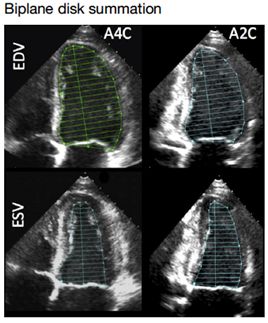

➤ 1.2 左心室测量(容积)

心尖四腔心与两腔心切面

1、校正形态改变;

2、几何假设较线性指标少;

3、心尖缩短常见;

4、心内膜回声失落;

5、不能评价心尖两腔心与四腔心切面以外的形态改变。